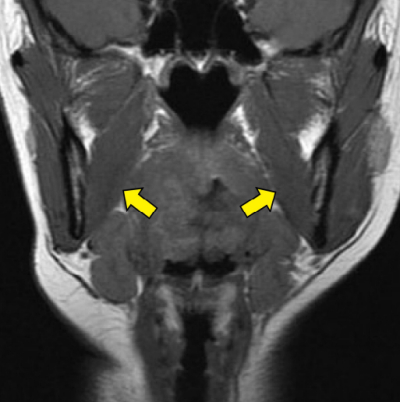

ヒト顔面部の MRI T1強調像を別に示す。矢印で示すのはどれか。1つ選べ。

a. 咬 筋

b. 側頭筋

c. 顎二腹筋

d. 外側翼突筋

e. 内側翼突筋